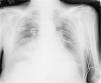

Varón de 78 años ingresado en cuidados intensivos por hematoma subdural con desarrollo de síndrome de distrés respiratorio agudo (SDRA) por neumonía nosocomial y desconexión prolongada de la ventilación mecánica invasiva. Traqueostomizado y precisando gastrostomía percutánea (PG) se inicia ventilación mecánica no invasiva (VMNI) como apoyo en retirada de respirador, desarrollando neumoperitoneo en radiografía de control (fig. 1) de manera asintomática, descartándose perforación de víscera hueca o complicaciones de la PG mediante prueba de imagen con contraste oral (figs. 2 y 3). La VMNI es causa muy infrecuente de neumoperitoneo benigno a tener en cuenta en pacientes ventilados y portadores de gastrostomía. El tratamiento debe ser conservador.